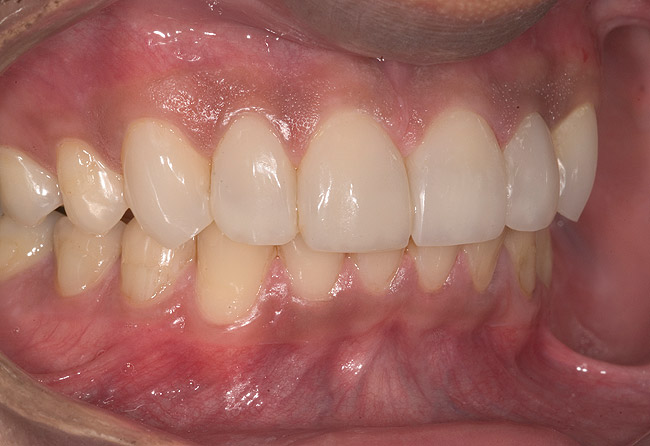

Figure 16  1:2 right lateral view; posteriors discluded in MIP.

Figure 16

Figure 17  1:2 left lateral view; posteriors discluded in MIP.

Figure 17